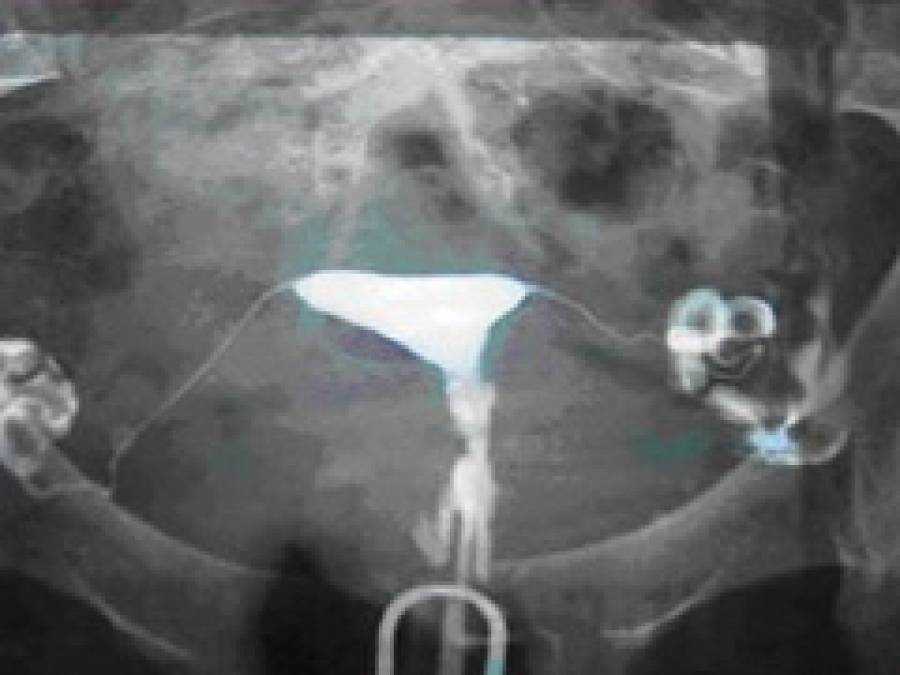

Гистеросальпингография: описание и фотографии